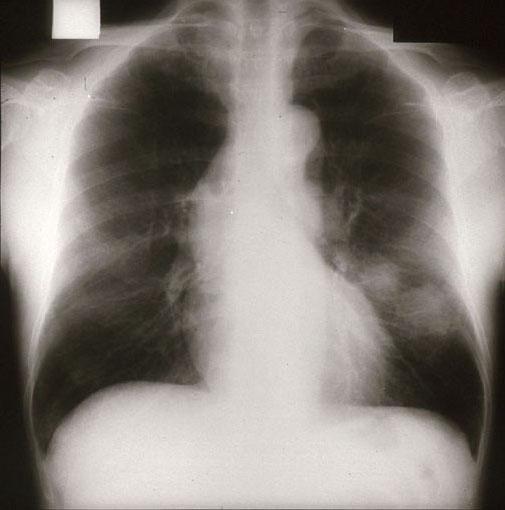

症例提示(所在地,施設名等): 東京都・ 国立がんセンター中央病院と九州がんセンターの共同作成

TIC症例

症例登録日 2001/11/26

画像数 22

性別 男性

年齢 60-64

画像ID:2618

[ 画像ID:2618 ]

部位(臓器別)その他/

検査方法X-P